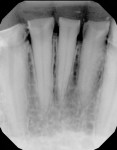

A 36-year-old male patient was referred for specialty care to coordinate a combined periodontal-prosthodontic treatment. The patient had a medical diagnosis of autism that required 24-hour home supervision as well as a history of incomplete restorative dentistry, bruxism, regurgitation, acid erosion, over-retained stainless steel crowns, enamel dysplasia, occlusal disharmony, teeth without clinical crowns, and major esthetic compromise. His condition resulted from a lack of an organized approach to oral care and rehabilitation. The patient's chief complaints were pain, tooth sensitivity, and difficulty eating. In addition, he had a history of excessive grinding and clenching of the teeth. Clinical and radiographic evaluations were performed, which revealed a severely worn-down dentition (Figure 1). In order to facilitate the necessary prosthodontic treatment that the patient required to regain dental function and improve his speech and esthetics, surgical crown lengthening was recommended. Following crown lengthening, the patient would be restored with dental crowns for teeth Nos. 19 through 30. This treatment plan was accepted by the patient and his caregivers.